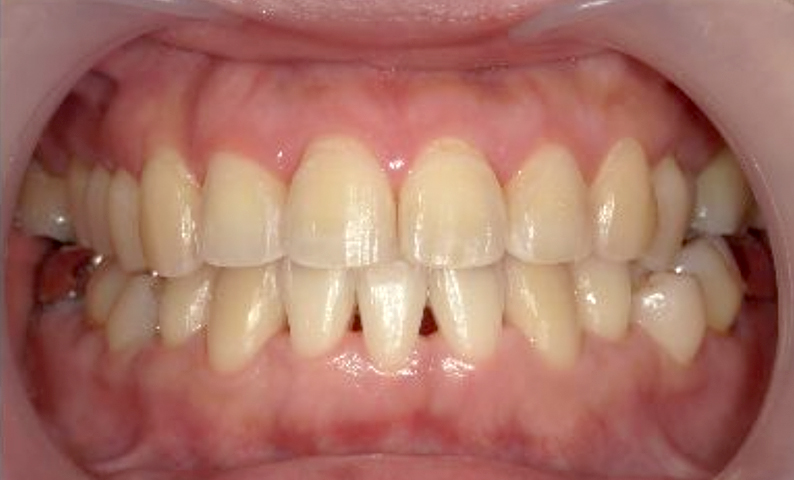

症例_002 上顎だけの部分矯正

治療期間:7ヶ月金額:30万円+税女性前歯のガタガタ上の前歯だけ

| Before | After |